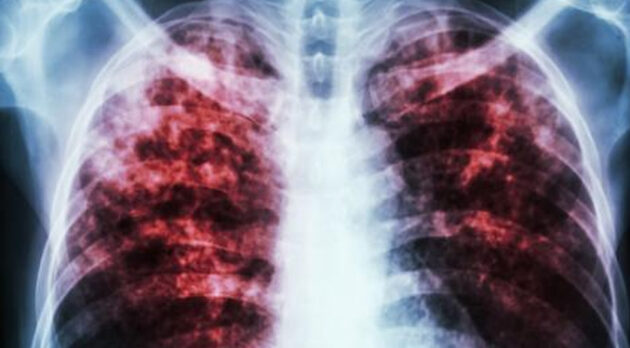

El taller incluirá presentaciones técnicas y visitas a centros de salud para conocer la implementación de los tratamientos acortados, y también abordará los avances del país en el uso de nuevas tecnologías de diagnóstico, como la biología molecular y la inteligencia artificial aplicada al diagnóstico por imágenes.

Por: Agencias / Foto: Cortesía